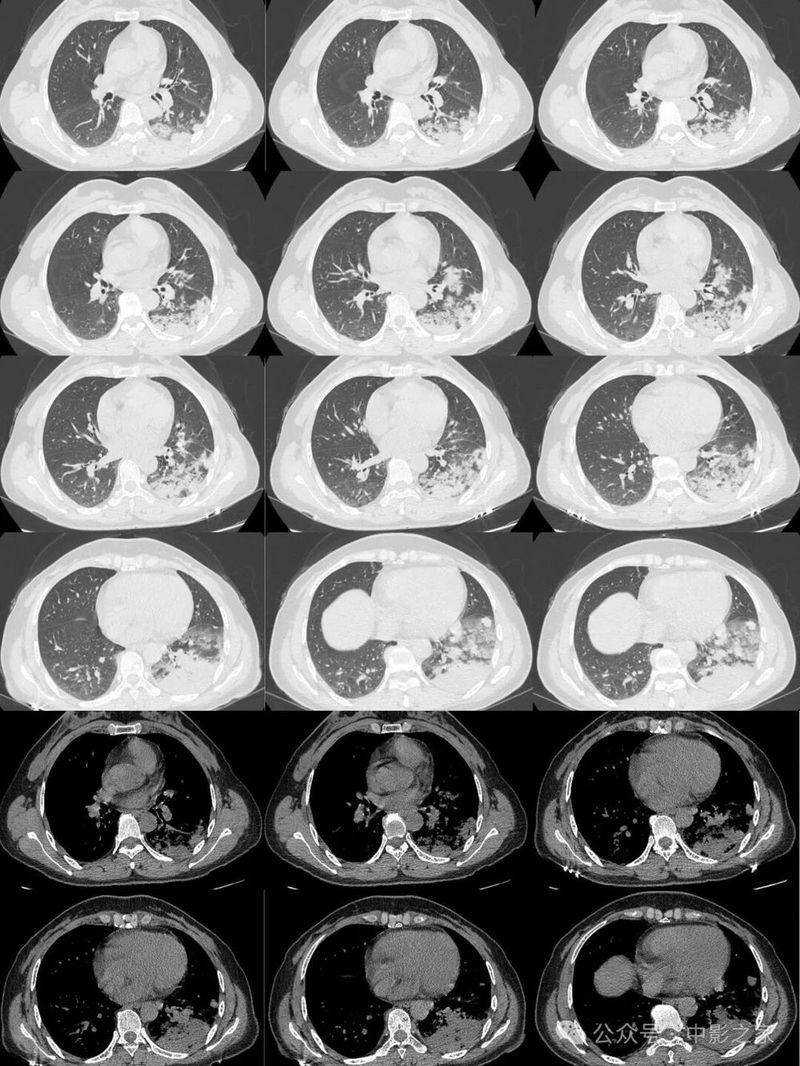

一、结节肿块型

1、部位:一般位于胸膜下,背侧胸膜下为主,两下肺明显,上肺偏少(3/4位于下叶 )

肺泡巨噬细胞吞噬肺隐球菌后根植于肺循环末梢血流缓慢或停滞处的肺外周带。

2、与胸膜关系:2/3与胸膜之间有空隙,1/3与胸膜相连,表现为糊墙征(附近胸膜增厚、胸膜外脂肪间隙增宽)

3、大小:结节较小,多为2cm以下;

4、边缘:绝大部分边界清楚,边缘可见平直征、刀切征,可以有细小毛刺,比较纤细,多为晕征中毛刺,相对收缩力偏弱;少数病人收缩比较明显

5、密度及强化:实性部分密度均匀,约1/3内部可见空泡征、实变中的空洞或空腔(可以单个内壁光滑,也可以多分隔)、含气支气管征;增强后均匀强化(强化轻到中度)延迟强化;

6、与血管的关系:2/3近端与血管相连,部分血管自然穿过;

7、晕征:1/3有晕征,晕多范围较小,个别晕较大。

二、浸润实变型

1、分布多为下叶胸膜下

2、实变区密度均匀;

3、大部分病灶与胸膜相连(95%),糊墙征(个别可以栽赃)

4、晕征:大部分有,晕的大小不一致,相对而言实变区密度偏低的晕范围大一些,约20%无晕征;

5、实变区密度均匀或内部有片状低强化(各自占一半左右),且延迟强化;

6、实变区大部分边界清楚,有刀切征、平直征;20%边界稍模糊,30%周围有毛刺征;

7、含气支气管征与密度、晕征的关系:支气管可以直达远端,也可以近端堵塞,堵塞处支气管正常或稍扩张,走形正常;密度密实程度越高晕征越少,含气支气管近端堵塞的几率越高:如果周围晕征明显,密度偏低,边界欠清晰,含气支气管会直达远端;

8、空洞:约50%见到空洞或空腔,内壁光滑,可以多个组成,周围无坏死,内部无液平,可以有残余结构,个别内壁欠光滑;

9、近端均与血管相连。